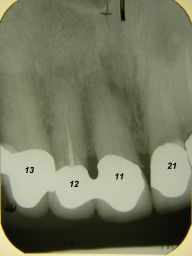

Weil auch die anderen Schneidezahnkronen (12-22) durch Randreparaturen und den schlechten Randschluß erneuerungsbedürftig aussahen, wurden 4 Einzelkronen geplant. Vorher hieß es aber noch, die schlechte Wurzelfüllung im Zahn 12 (Röntgenbild links) besser zu machen. Hierfür wurden am 17.2.06 die alten Kronen 11 und 12 entfernt. Rechts das Bild nach Entfernung von alten Füllungen und Karies. | |